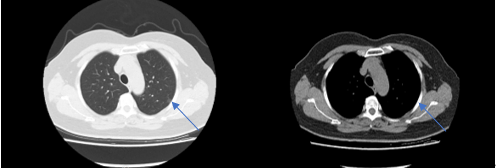

▲CT检查提示左上肺直径约1cm的肺结节